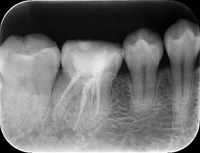

• 根管充填

レントゲン画像

可能な限り根の細菌を減らした後、根管充填材を根に緊密に充填し、細菌が増殖し得るスペースを無くします。